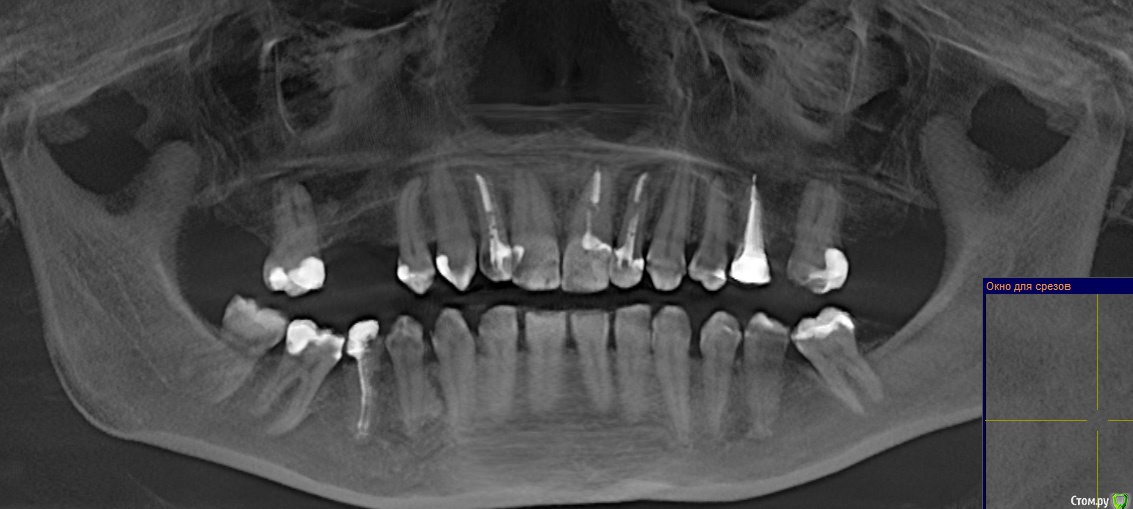

Ankazabolevshaya Опубликовано 28 мая, 2016 Поделиться Опубликовано 28 мая, 2016 Здравствуйте, уважаемые врачи! Очень сильно нуждаюсь в вашей помощи. В 2013 мне лечили два передних зуба (клык и передний). Пломбировали каналы, но коронки не ставили. Этой зимой я почувствовала боль в передних зубах в районе челюсти. Раздражение в дёснах. Резь. Потом вылез какой-то пупырь на десне. Я думала, что это стоматит. Не верила тем, кто мне говорил про нужность обзорного снимка. Признаю свою глупость. Теперь, после КТ оказалось что у меня сломаны эти каналы, а под левым клыком пустота. А пупырь, как мне сказали - это выход свища.Мне предложили зуб удалять. Как-то восстанавливать эту пустоту. Потом делать имплантацию. Есть ли сегодня технологии, позволяющие восстанавливать это пространство под зубом без его удаления, с последующей коронкой на него? И ещё один вопрос: могло ли все это случится из-за какой-нибудь заразы, занесенной во время лечения этих двух зубов в 2013г. ? Так же был момент ранения слизистой левой ноздри, как раз над свищем, который на десне. Просто очень часто слизистая иссыхала в одном месте и я травмировала слизистую. Буду очень благодарна за ответ. От меня в клинике ждут решения, а я переживаю, что улыбка испортится с искусственным зубом. Зуб этот свой очень люблю. Анна. Ссылка на комментарий

red_butler Опубликовано 28 мая, 2016 Поделиться Опубликовано 28 мая, 2016 Спасибо! Можете пояснить, Вы думаете, что зуб можно спасти? если судить только по снимкам, то да 1 Ссылка на комментарий

red_butler Опубликовано 29 мая, 2016 Поделиться Опубликовано 29 мая, 2016 а скажите, как по Вашему, это киста прикорневая? Или челюсть разрушена? Нужно восстановление челюсти? это не важно и корень ведь сломан, поставить под коронки всё равно можно? перелома не увидел И еще последнее, как Вы относитесь к процедуре - депофорез? В моём случае стоит в эту торону смотреть? бесполезно 2 Ссылка на комментарий